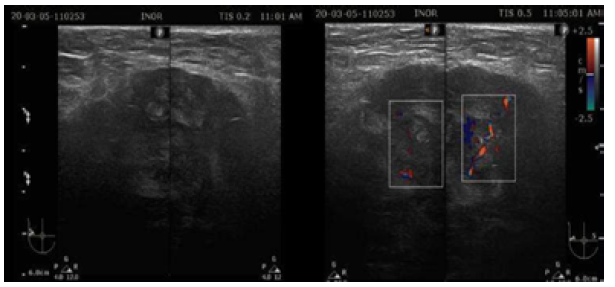

Ultrasound showed that the left breast had no alterations, but the right breast had a fatty breast pattern, an extensive solid nodular area located in the upper outer quadrant and axillary extension, microlobulated margins associated with skin thickening (6mm), and signs of lymphedema of the subcutaneous cellular tissue. This examination established that the right breast lesion was classified as BI-RADS 5; in addition, the right axilla showed lymph nodes classified as BRN-4 according to Rostagno's classification, which corresponds to lymph nodes >3.5mm in size with increased thickness and/or focal thickening of the cortex (Figure 1).

Mammography also showed that the left breast had no alterations, and that the right breast had a fatty breast pattern, increased size with global diffuse distortion of the glandular architecture, skin thickening (6 mm), and trabecular thickening of the subcutaneous cellular tissue. It was also noteworthy that there was an oval nodule with indeterminate margins, approximately 110x84mm, without calcifications and located in the upper outer quadrant towards the axillary extension, as well as lymph nodes with a metastatic appearance in the right axilla. Based on this examination, the right breast lesion was also classified as BI-RADS 5 (Figure 2).

On March 18, 2020, the patient was reassessed during a follow-up consultation by the breast care service, and in view of the ultrasound and mammography findings, confirmatory studies (ultrasound-guided automated TRU-CUT needle biopsy) and extension studies (computed axial tomography, magnetic resonance imaging, and blood analysis panel) were performed. Thus, the following day, a simple computed axial tomography of the thorax and abdomen with coronal reconstruction was performed, which showed the following findings (Figure 3):

• Hypodense solid mass with irregular borders in the upper outer quadrant of the right breast towards the axillary extension, without calcifications and without infiltration of the pectoralis major muscle.

• Metastatic lymph nodes in the right axilla.

• No metastases in the pleura, lungs and solid organs of the abdomen; no secondary bone lesions were identified.

Patient's computed axial tomography.

Figure 3: Patient's computed axial tomography.

Source: Image obtained while conducting the study.